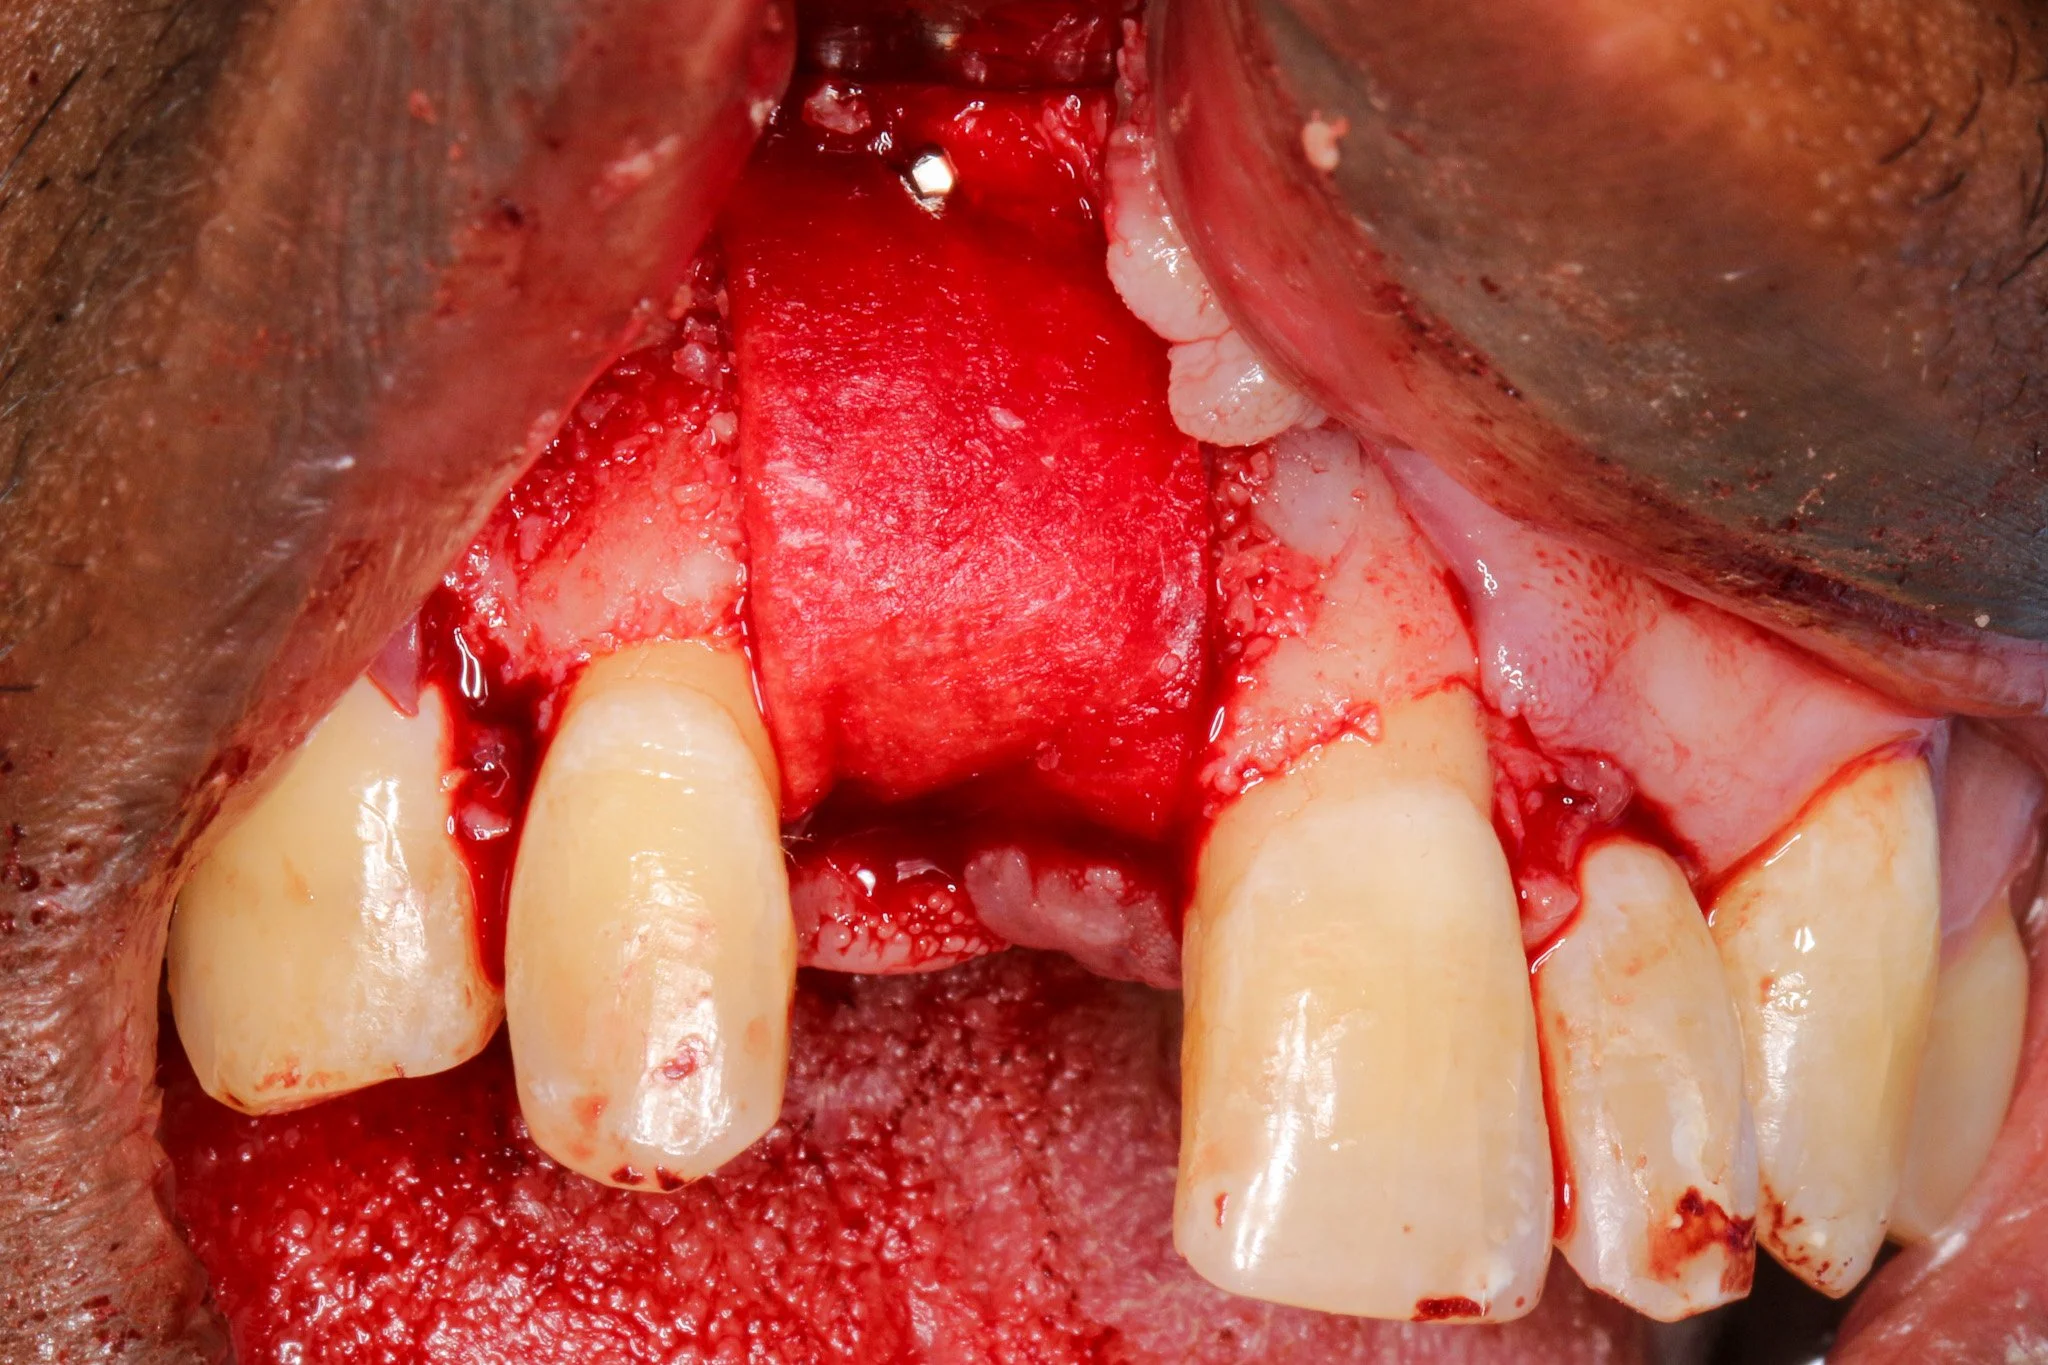

4 to 5 mm buccal bone dehiscence with concave morphology.

As you can see, there is a buccal-palatal concavity from the axial view on #8. Thus, GBR was planned for horizontal ridge augmentation to address a significant buccal bone dehiscence.

Periosteal releasing incision was executed to achieve tennsion-free, passive primary closure. Wang and colleagues 2001 demonstrated that passive flap closure significantly reduces membrane exposure rates and enhances bone regeneration outcomes. It is important to preserve blood supply to soft tissue while allowing adequat flap advancement when periosteal releasing incision is made.

A double-layer resorbable membrane technique was employed with tacking srew fixation to ensure graft stability and space maintenance. The use of resorbable membranes has been extensively validated in the literature, with systematic reviews by Rocchietta et al. (2008) confirming comparable outcomes to non-resorbable membranes while eliminating the need for 2nd stage surgery. Urban et al. (2009), the dual-membrane approach provides enhanced barrier function and structural support.